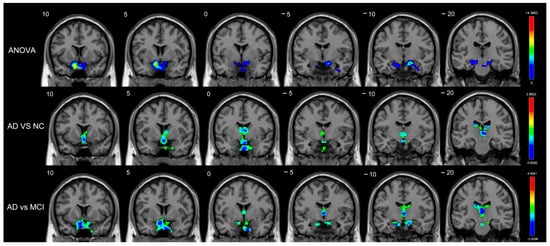

| MCI vs. NC | |||||

| Long-range | Amygdala_R | BA34 | (21,−2,−17) | 4.4157 | 38 |

| Amygdala_L | - | (−13,2,−15) | 3.3582 | 6 | |

| Putamen_L | BA25 | (−14,7,−9) | 3.2804 | 7 | |

| Pallidum_R | BA25 | (12,3,−5) | 3.1270 | 5 | |

| AD vs. NC | |||||

| Short-range | Caudate_L | - | (−7,1,11) | −2.9712 | 29 |

| Caudate_R | - | (9,5,7) | −2.8622 | 8 | |

| AD vs. MCI | |||||

| Short-range | Caudate_L | - | (−18,−21,23) | −3.2570 | 9 |

| Caudate_R | - | (16,−18,21) | −2.8545 | 4 | |

| Long-range | Caudate_L | - | (−15,14,18) | −3.7649 | 66 |

| Caudate_R | - | (17,6,23) | −3.7601 | 54 | |

| Amygdala_R | BA48 | (19,2,−11) | −3.6551 | 20 | |

| Pallidum_R | BA48 | (19,−3,−2) | −3.4747 | 9 |